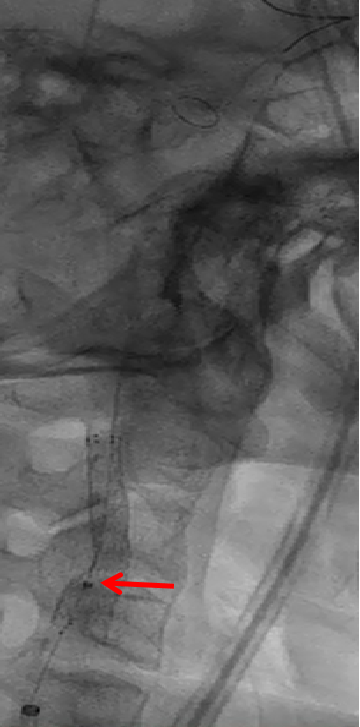

案例2

造影血流形态、残余狭窄均可以接受,切线位造影时发现有支架丝伸入到管腔,这样有可能造成涡流,发生内皮损伤,导致支架内再狭窄。这种情况做球囊后扩张,效果可能更好。